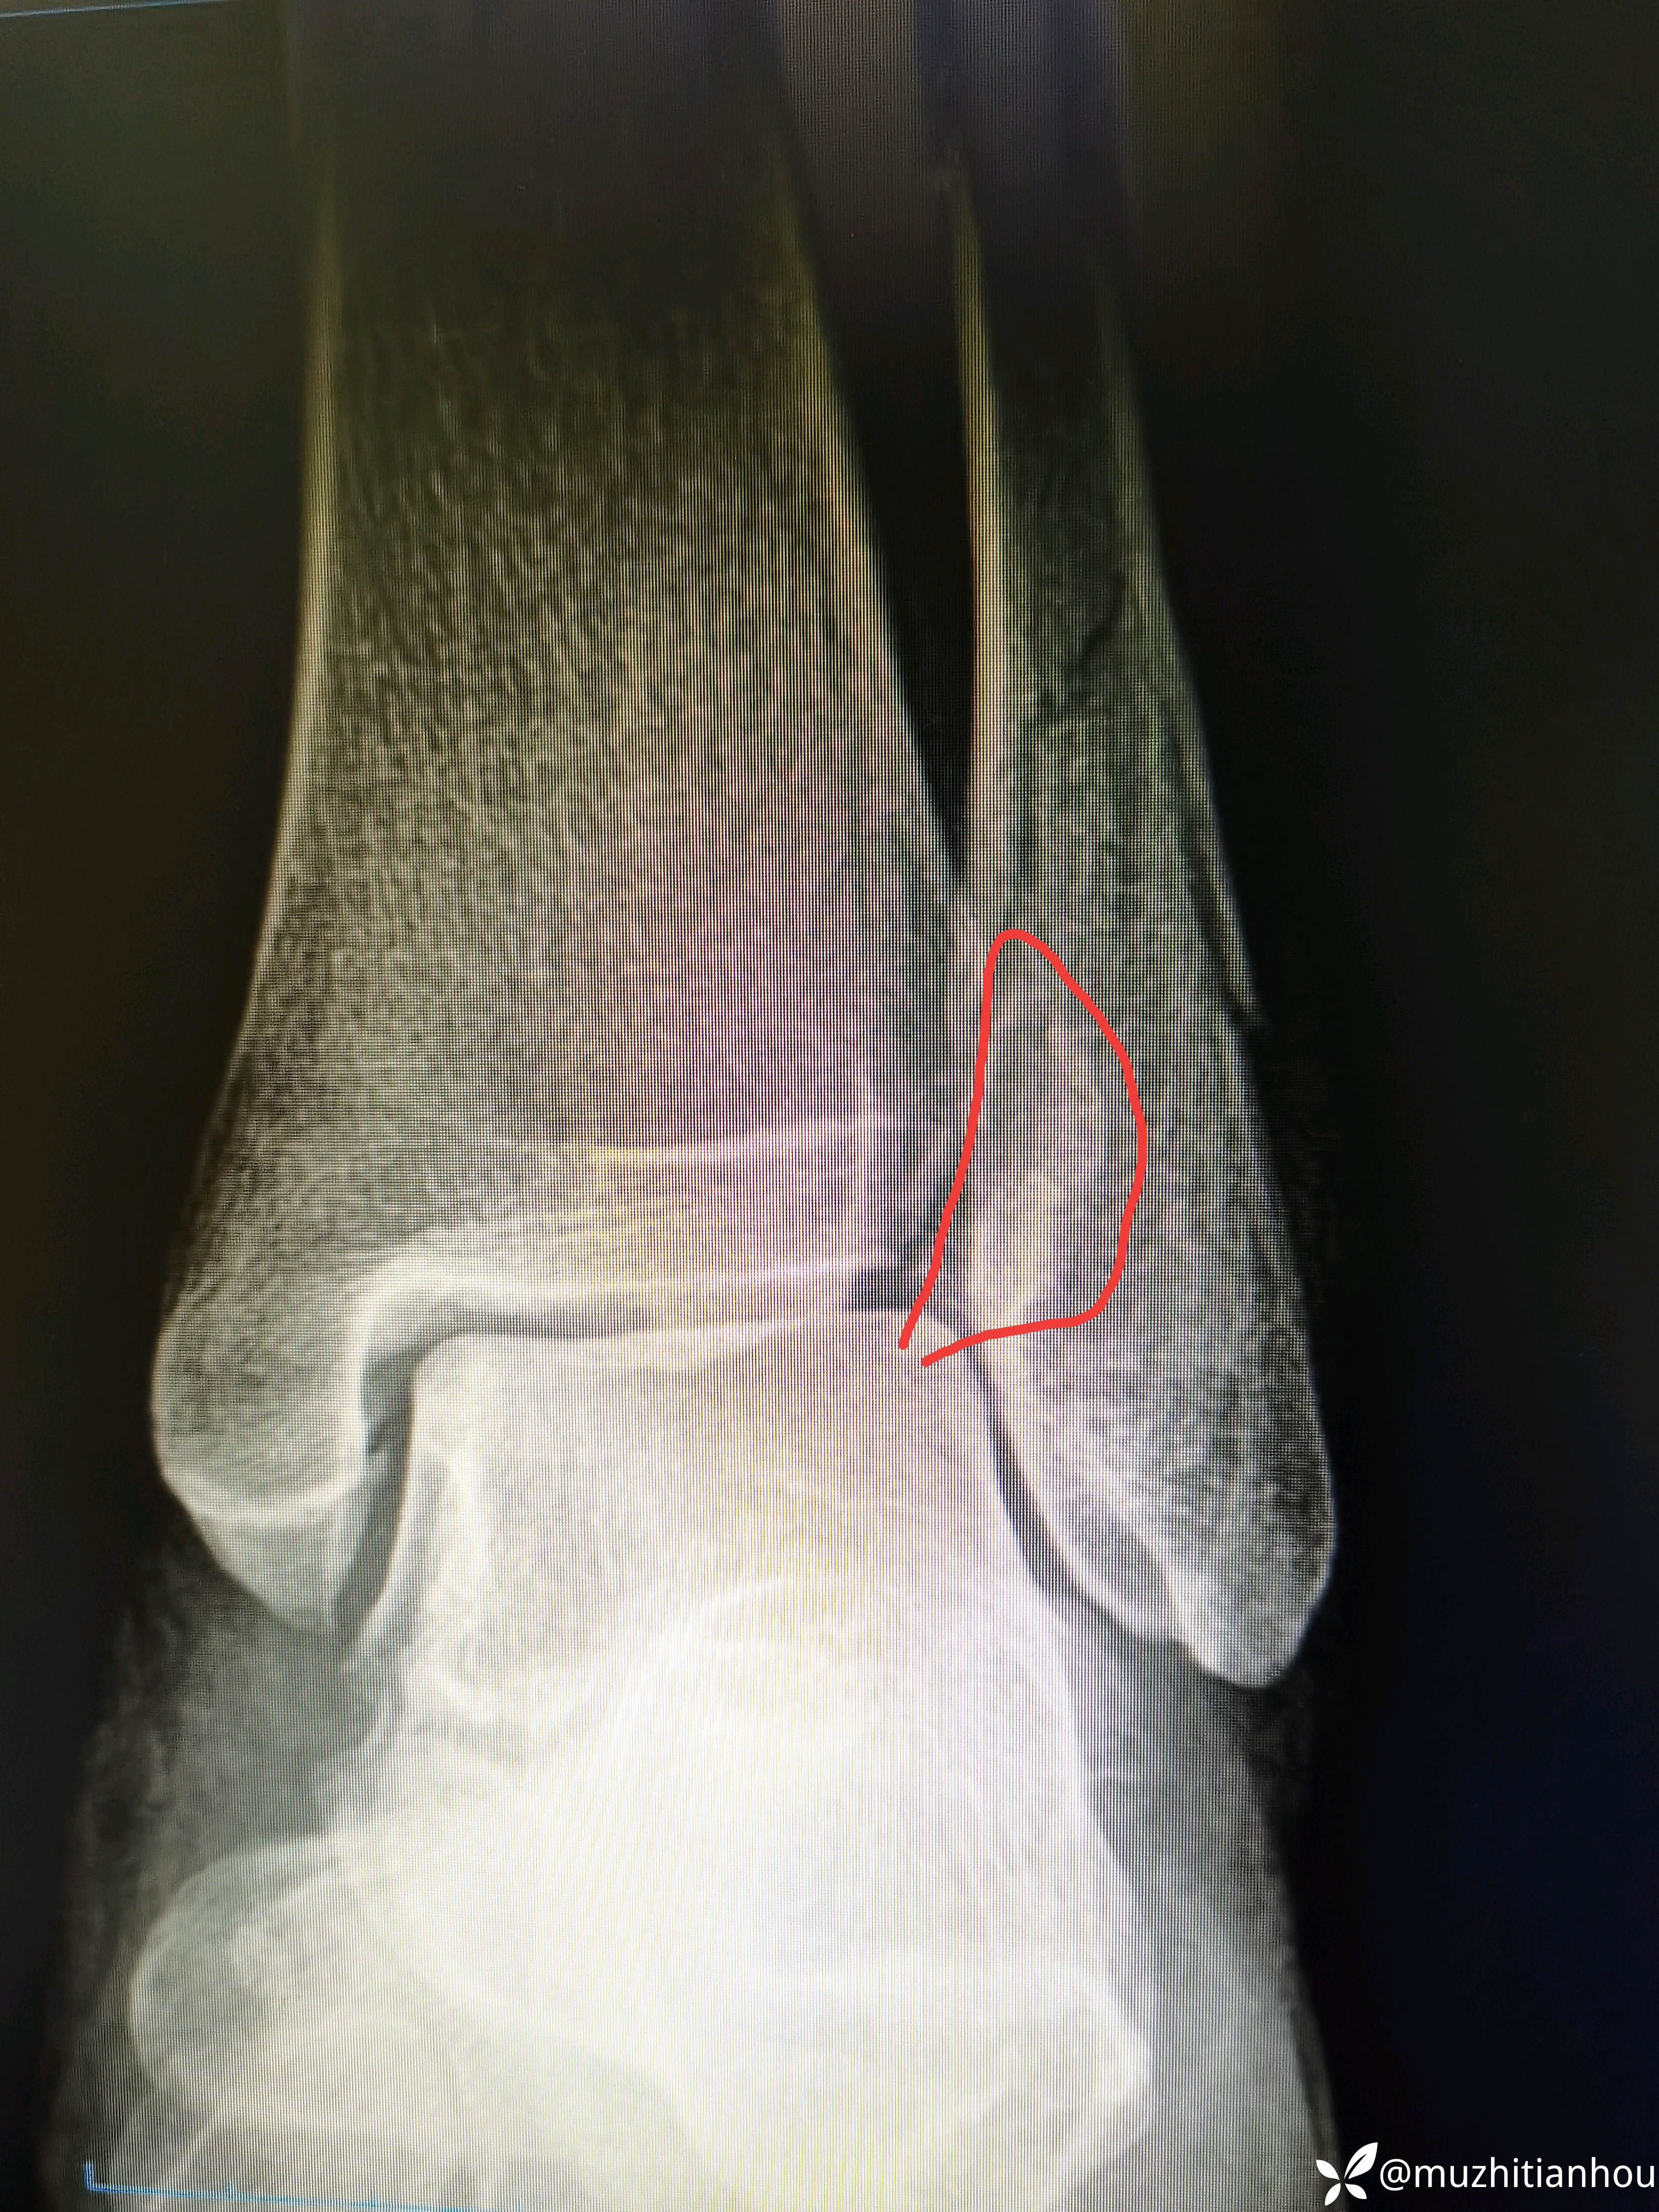

返回头来我们再阅片发现正位下胫腓存在骨块,存在分离移位,内踝侧位片骨折线前上后下亦存在分离移位,虽然腓骨长度没问题,但凭借这两处骨折和四度损伤样也完全说明手术指征明确。

内踝看到了移位,没有想象的那么好。

沈通氏线中段,tillaux骨块累及到下胫腓